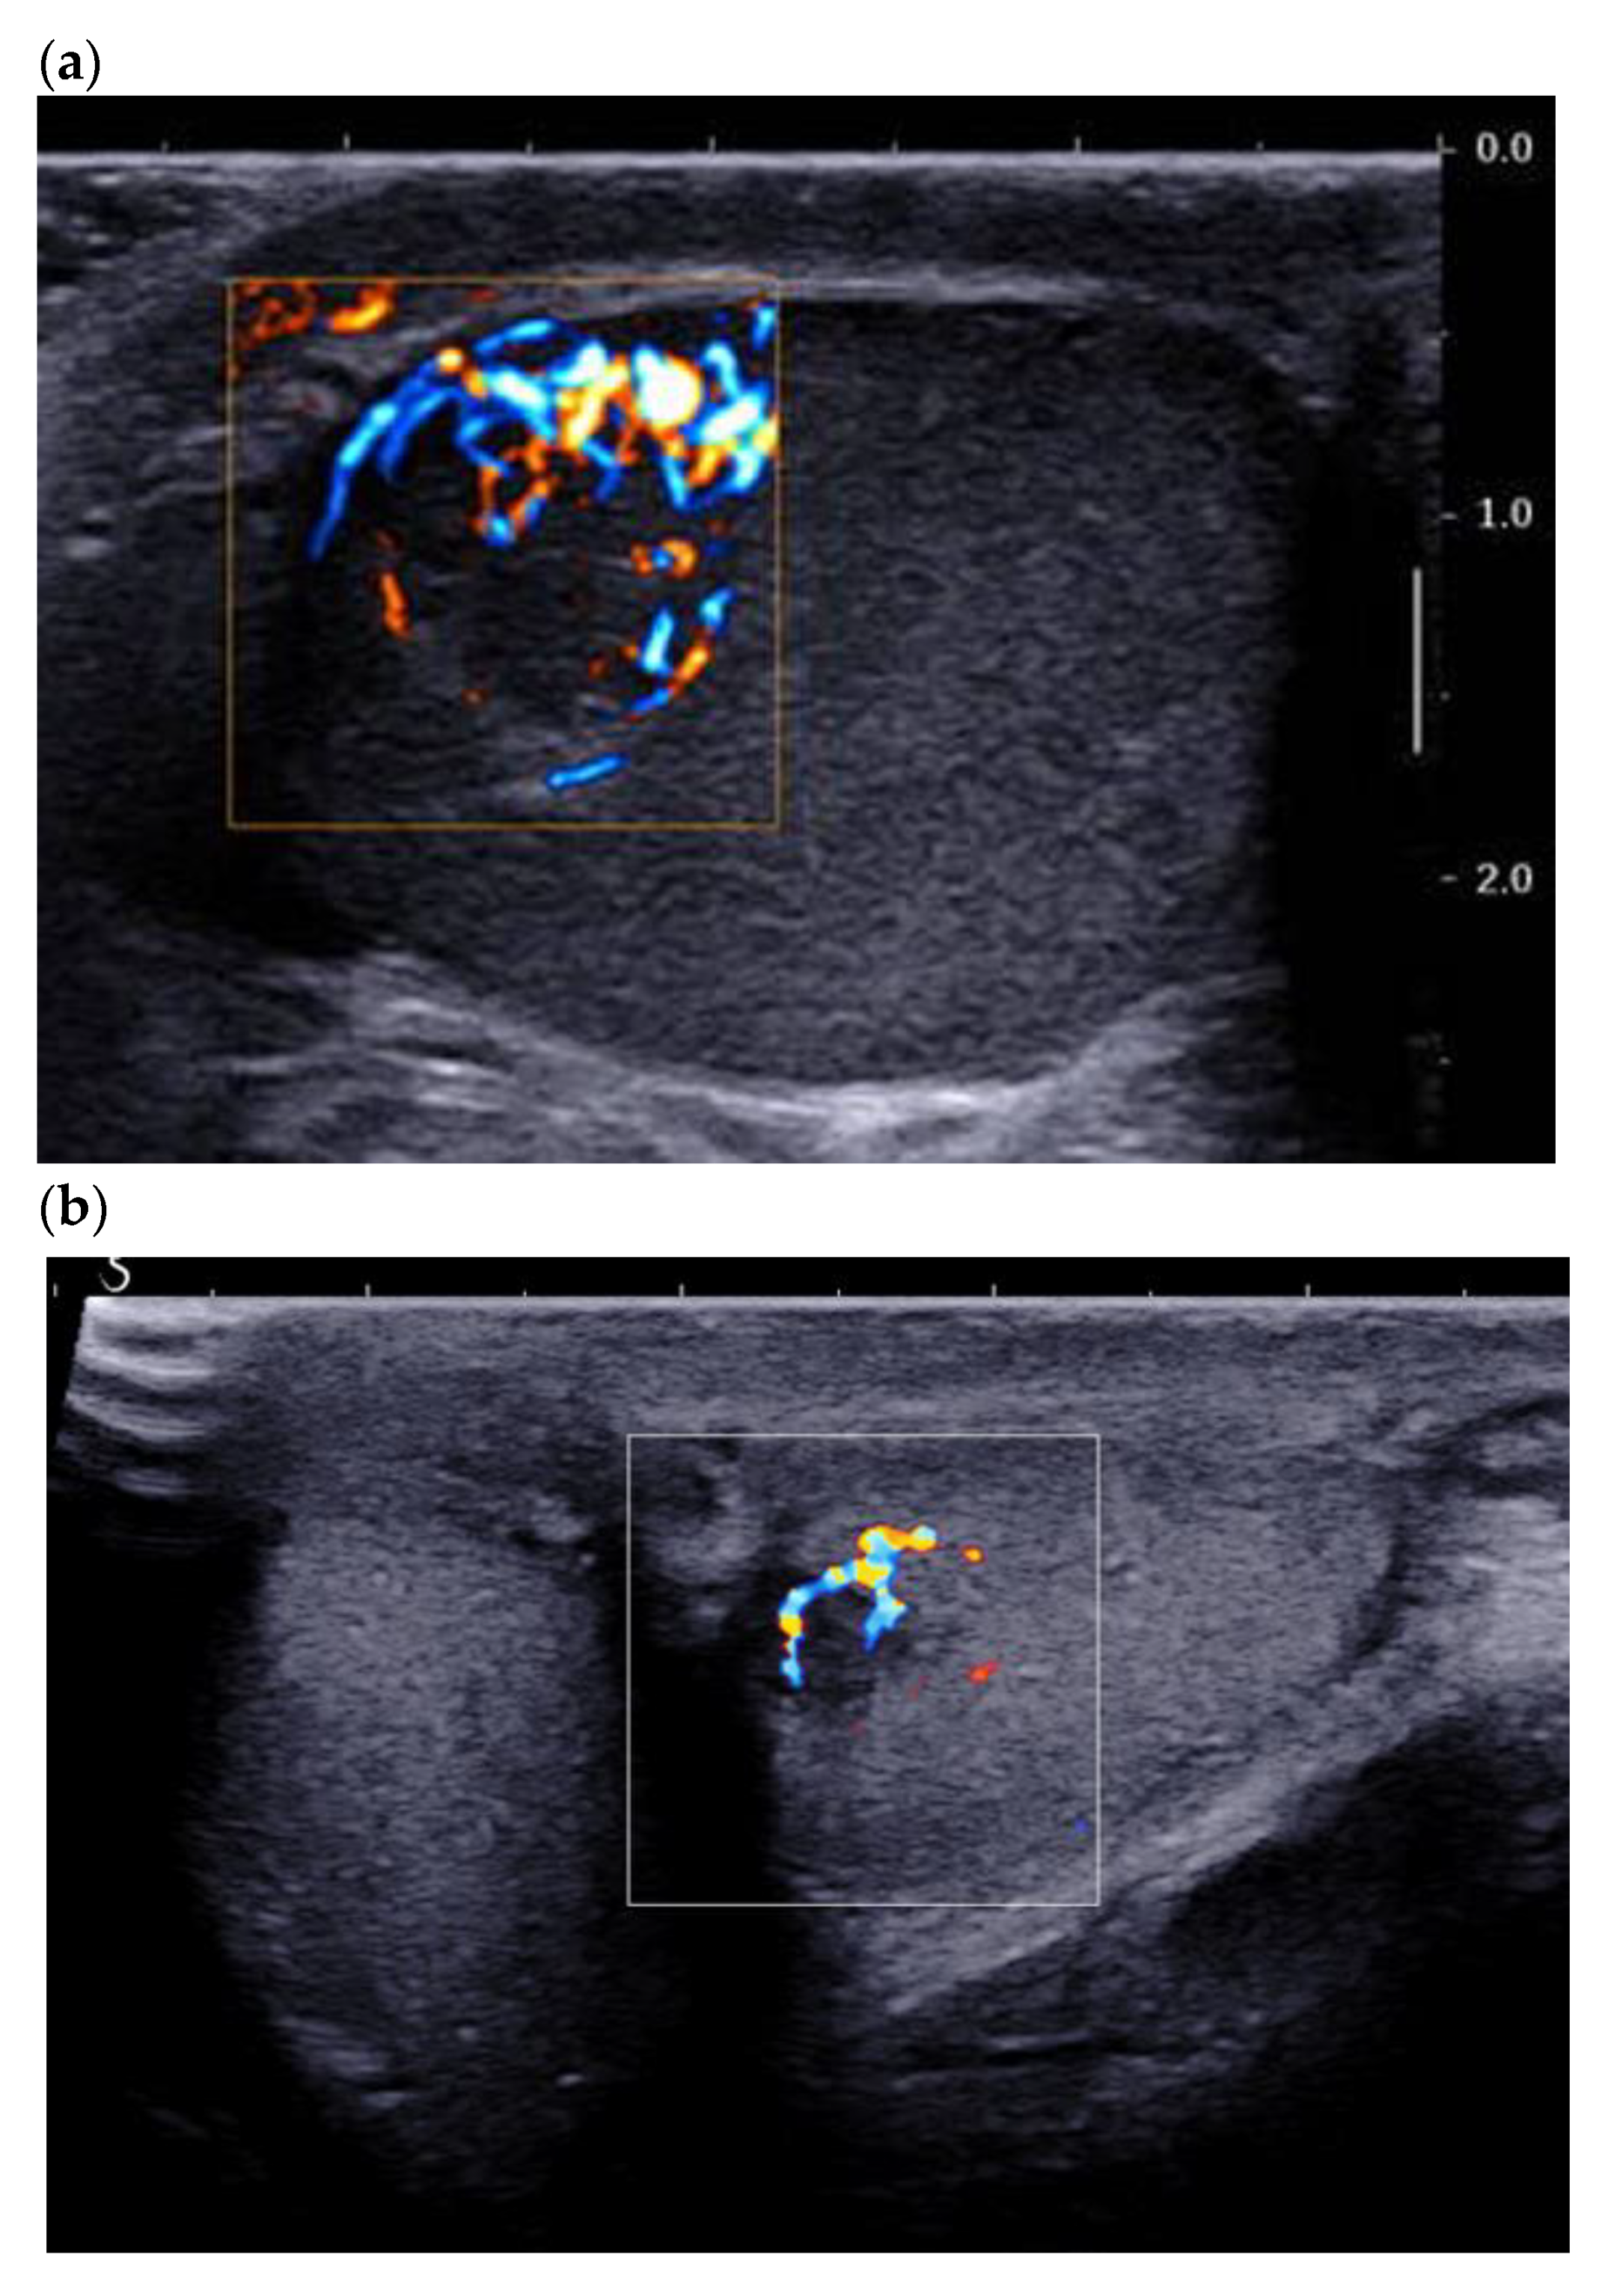

Klinefelter syndrome (KS) or 47,XXY (gonosomal aneuploidy) affects 0.1–0.2% of the general population, but the incidence rises to 3.1% in the infertile population [34]. Patients with KS are therefore regularly encountered during an infertility work-up. The ultrasound appearance of the testicles of KS patients is characteristic, and it should alert the radiologist. Rocher et al. recorded the scrotal ultrasound exams of 67 infertile men with KS and 66 non-KS non-obstructive azoospermic men, with histological comparison [9]. The KS patients had severe testicular hypotrophy (mean testis volume 2 mL), and a coarse or micronodular (nodules < 3 mm) echotexture versus a normal/striated echotexture in the infertile non-KS patients. The KS patients presented increased bilateral and symmetrical microlithiasis, unlike the infertile non-KS patients (28% vs. 4.5%). Histology confirmed that the nodules detected in KS patients were benign LCTs associated with Leydig cell hyperplasia surrounded by Sertoli cell involution and seminiferous tubule degeneration. Some patients present with mosaic Klinefelter syndrome: an extra X chromosome in some cells with generally fewer symptoms. Our experience with mosaic Klinefelter syndrome is based on nine patients included in a series of 67 patients with KS syndrome: there were quite similar in testis volume (2 ± 0.9 mL versus 2.4 ± 1.44 mL per testis), testosterone level (10.1 ± 5.2 nmol/mL versus 11.1 ± 4.85 mL), and FSH level (33.7 ± 16.2 UI/L versus 28.9 ± 11.5 UI/L) [9]. Severe testicular hypotrophy with hypervascularized bilateral micronodules should prompt the radiologist to search for KS. Radical orchiectomy risks worsening the patient’s testosterone deprivation and should be avoided in this situation. Even though KS patients are supposed to be at risk of testicular germ cell tumors, it appears that most nodular anomalies of the testicle found in these patients are linked to Leydig cell hyperplasia/tumors (Figure 9). However, the radiologist should keep in mind that KS patients are at risk of extra gonadic germ cell tumors, especially located in the mediastinum [35].

Figure 9.

26-year-old patient addressed for infertility work up/Klinefelter’s syndrome follow up. Leydig cell hyperplasia in a patient with Klinefelter’s syndrome. (a) Two patients with major testicular hypotrophy (2 mL), with coarse echostructure and micronodules mostly hyperechoic. (b) Color Doppler ultrasound showing diffuse hypervascularization of the testicle, which contrasts with the relatively hypovascularized aspect of undescended testicles.